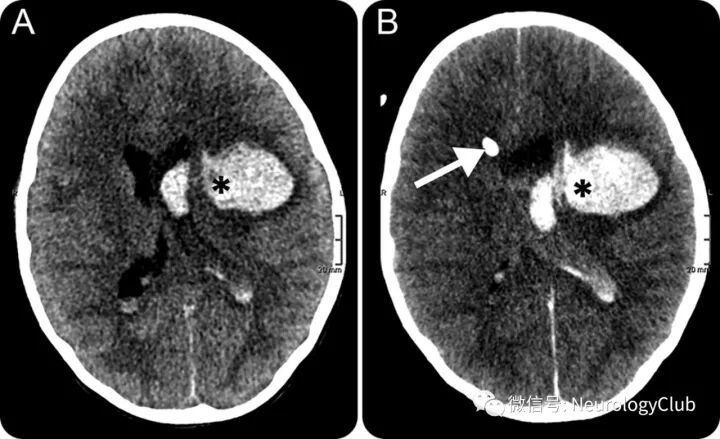

(图1:A:CT平扫可见左侧基底节区血肿伴轻度周围水肿,邻近顶枕叶可见陈旧性梗死灶;B:CTA原始图像上可见血肿内小灶强化,即点征;C:增强CT可见点征扩大,符合对比剂外渗;D:起病1天后复查CT平扫提示血肿扩大并破入脑室)

(图9:CT平扫[A]可见血肿内低密度区,即漩涡征[*],CT血管造影[B]可见高密度点征[箭];此时已经有占位效应伴中线移位和脑室内血肿

(图10:数小时后复查的CT可见置入脑室内引流管[箭],而血肿往内侧进一步延伸[*])